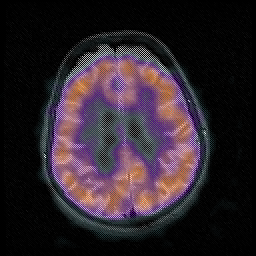

Huntington's Chorea, MR -- Slice #14

[Home][Help][Clinical] Slice 14